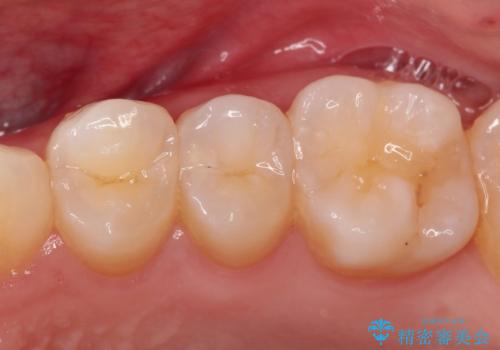

- 定期検診にてむし歯を認めたため、セラミックインレーにて修復を行いました。

e-max プレスインレーにて修復治療を行っているため適合性及び審美性の高い治療を行うことができます